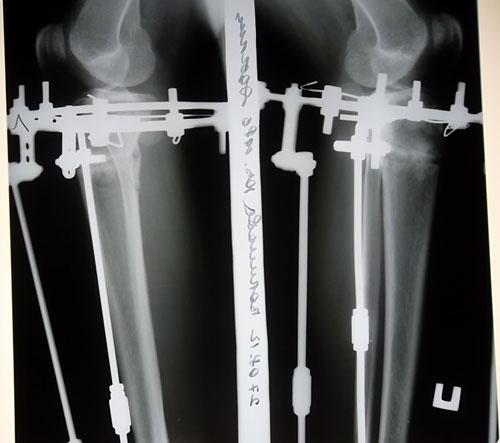

Вчера 13 июля у меня был день открытий. Утром, как всегда вставать было тяжело, около часа готовила себя к этому (зарядка, массажик, обезбол. таблетка - иногда). Сначала решила поменять простые ходунки, на ходунки с колесами (их не нужно постоянно переставлять, а значит и останавливаться не нужно, просто толкаешь вперед и все). Немного практики и вуоля, получилось шагать как нормальный человек, без остановок после каждого шага. К обеду хорошие люди принесли мне костыли. Когда в первый раз встаешь, есть страх упасть вперед, потом привыкаешь.Через пару часов уже чуть ли не бегала на них. Могу сказать, что на костылях ходить проще, ноги разрабатываются лучше и быстрее, однако, не переусердствуйте, у меня к вечеру болели подмышки. После обеда заходил Н.Н. сказал, что доволен моими рентген снимками (все как он любит кости ровные, костные отломки перекрывают друг друга, а значит срастутся быстро). Вообще, человек он очень позитивный

Кто-то ее сравнивает с походкой пингвина, кто-то с утиной, а по мне, так она напоминает походку зомби из фильмов ужасов (ноги еле отрываешь от пола и раскачиваешься в разные стороны). Но все-таки, это так здорово - ходить самой! Н.Н. сделал мне перемонтаж аппаратов, ходить стало намного удобнее, (боковые штыри теперь не цепляются друг об друга). Светлана Васильевна перевязала мои ранки, оказывается несколько спиц прорезали кожу, а я этого даже и не чувствовала (это очень хорошо). До сих пор удивляюсь

, глядя на то, как по 3 спицы пронизывают твою ногу насквозь в 4 местах, (прям как шашлык на шампурах) как это возможно - не ощущать адских болей при этом. Попробуй, проткни себе что-нибудь!? Тут иголкой уколишься и то больно. Аппараты потихонечку становятся частью меня. А меж тем, время летит быстро, завтра уже буду съезжать. И скучать, наверное, буду.

Сегодняшняя встреча боевых подруг. 3-е приехали на снятие аппаратов, а мы с Лучиком (крайние справа) на рентген контроль.